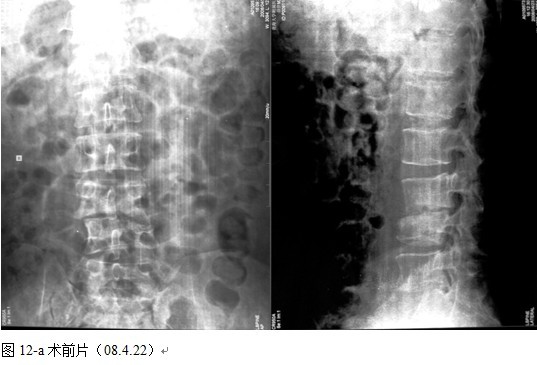

本组46例中男28 例,女18 例。年龄17~67岁,病程6 个月~7年,平均11.3 个月。本组患者均为 L1~S1腰段结核。病灶累及2 个椎体31例(L1-2 6例, L2-3 8例,L3-4 10例,L4-5 5例,L5-S1 2例),3 个或3 个以上椎体15例。合并腰大肌脓肿23列,所有患者均有腰背部疼痛,活动受限,双下肢感觉麻木19例,会阴部感觉减退12例,双下肢肌力减弱12例,腱反射减弱12例,术前后凸角(Cobb 角) <30°者12例, 30°~60°者28 例, >60°者6 例,Cobb角平均32.3°4例患者是二次手术。术前均行X线片、CT或者MRI检查。术后病理检查确诊为脊柱结核。

图11-a术前